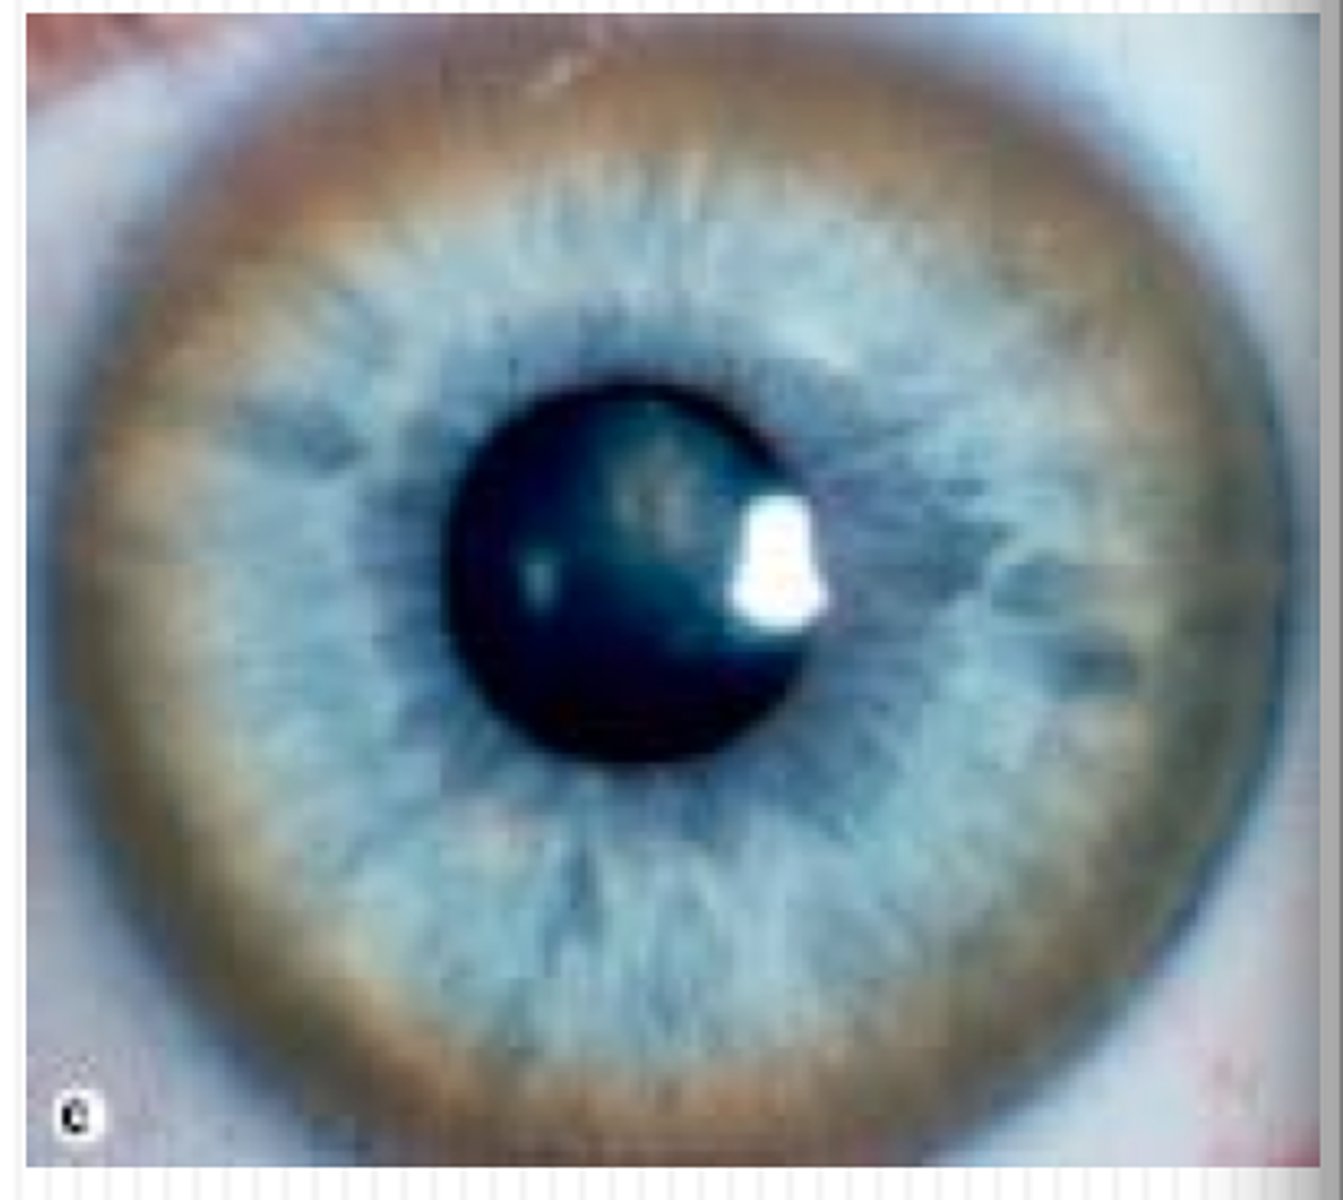

Golden brown rings around peripheral cornea

Kayser-Fleischer rings (copper accumulation from Wilson disease, check ceruloplasmin)

Risk of basal Ganglia atrophy